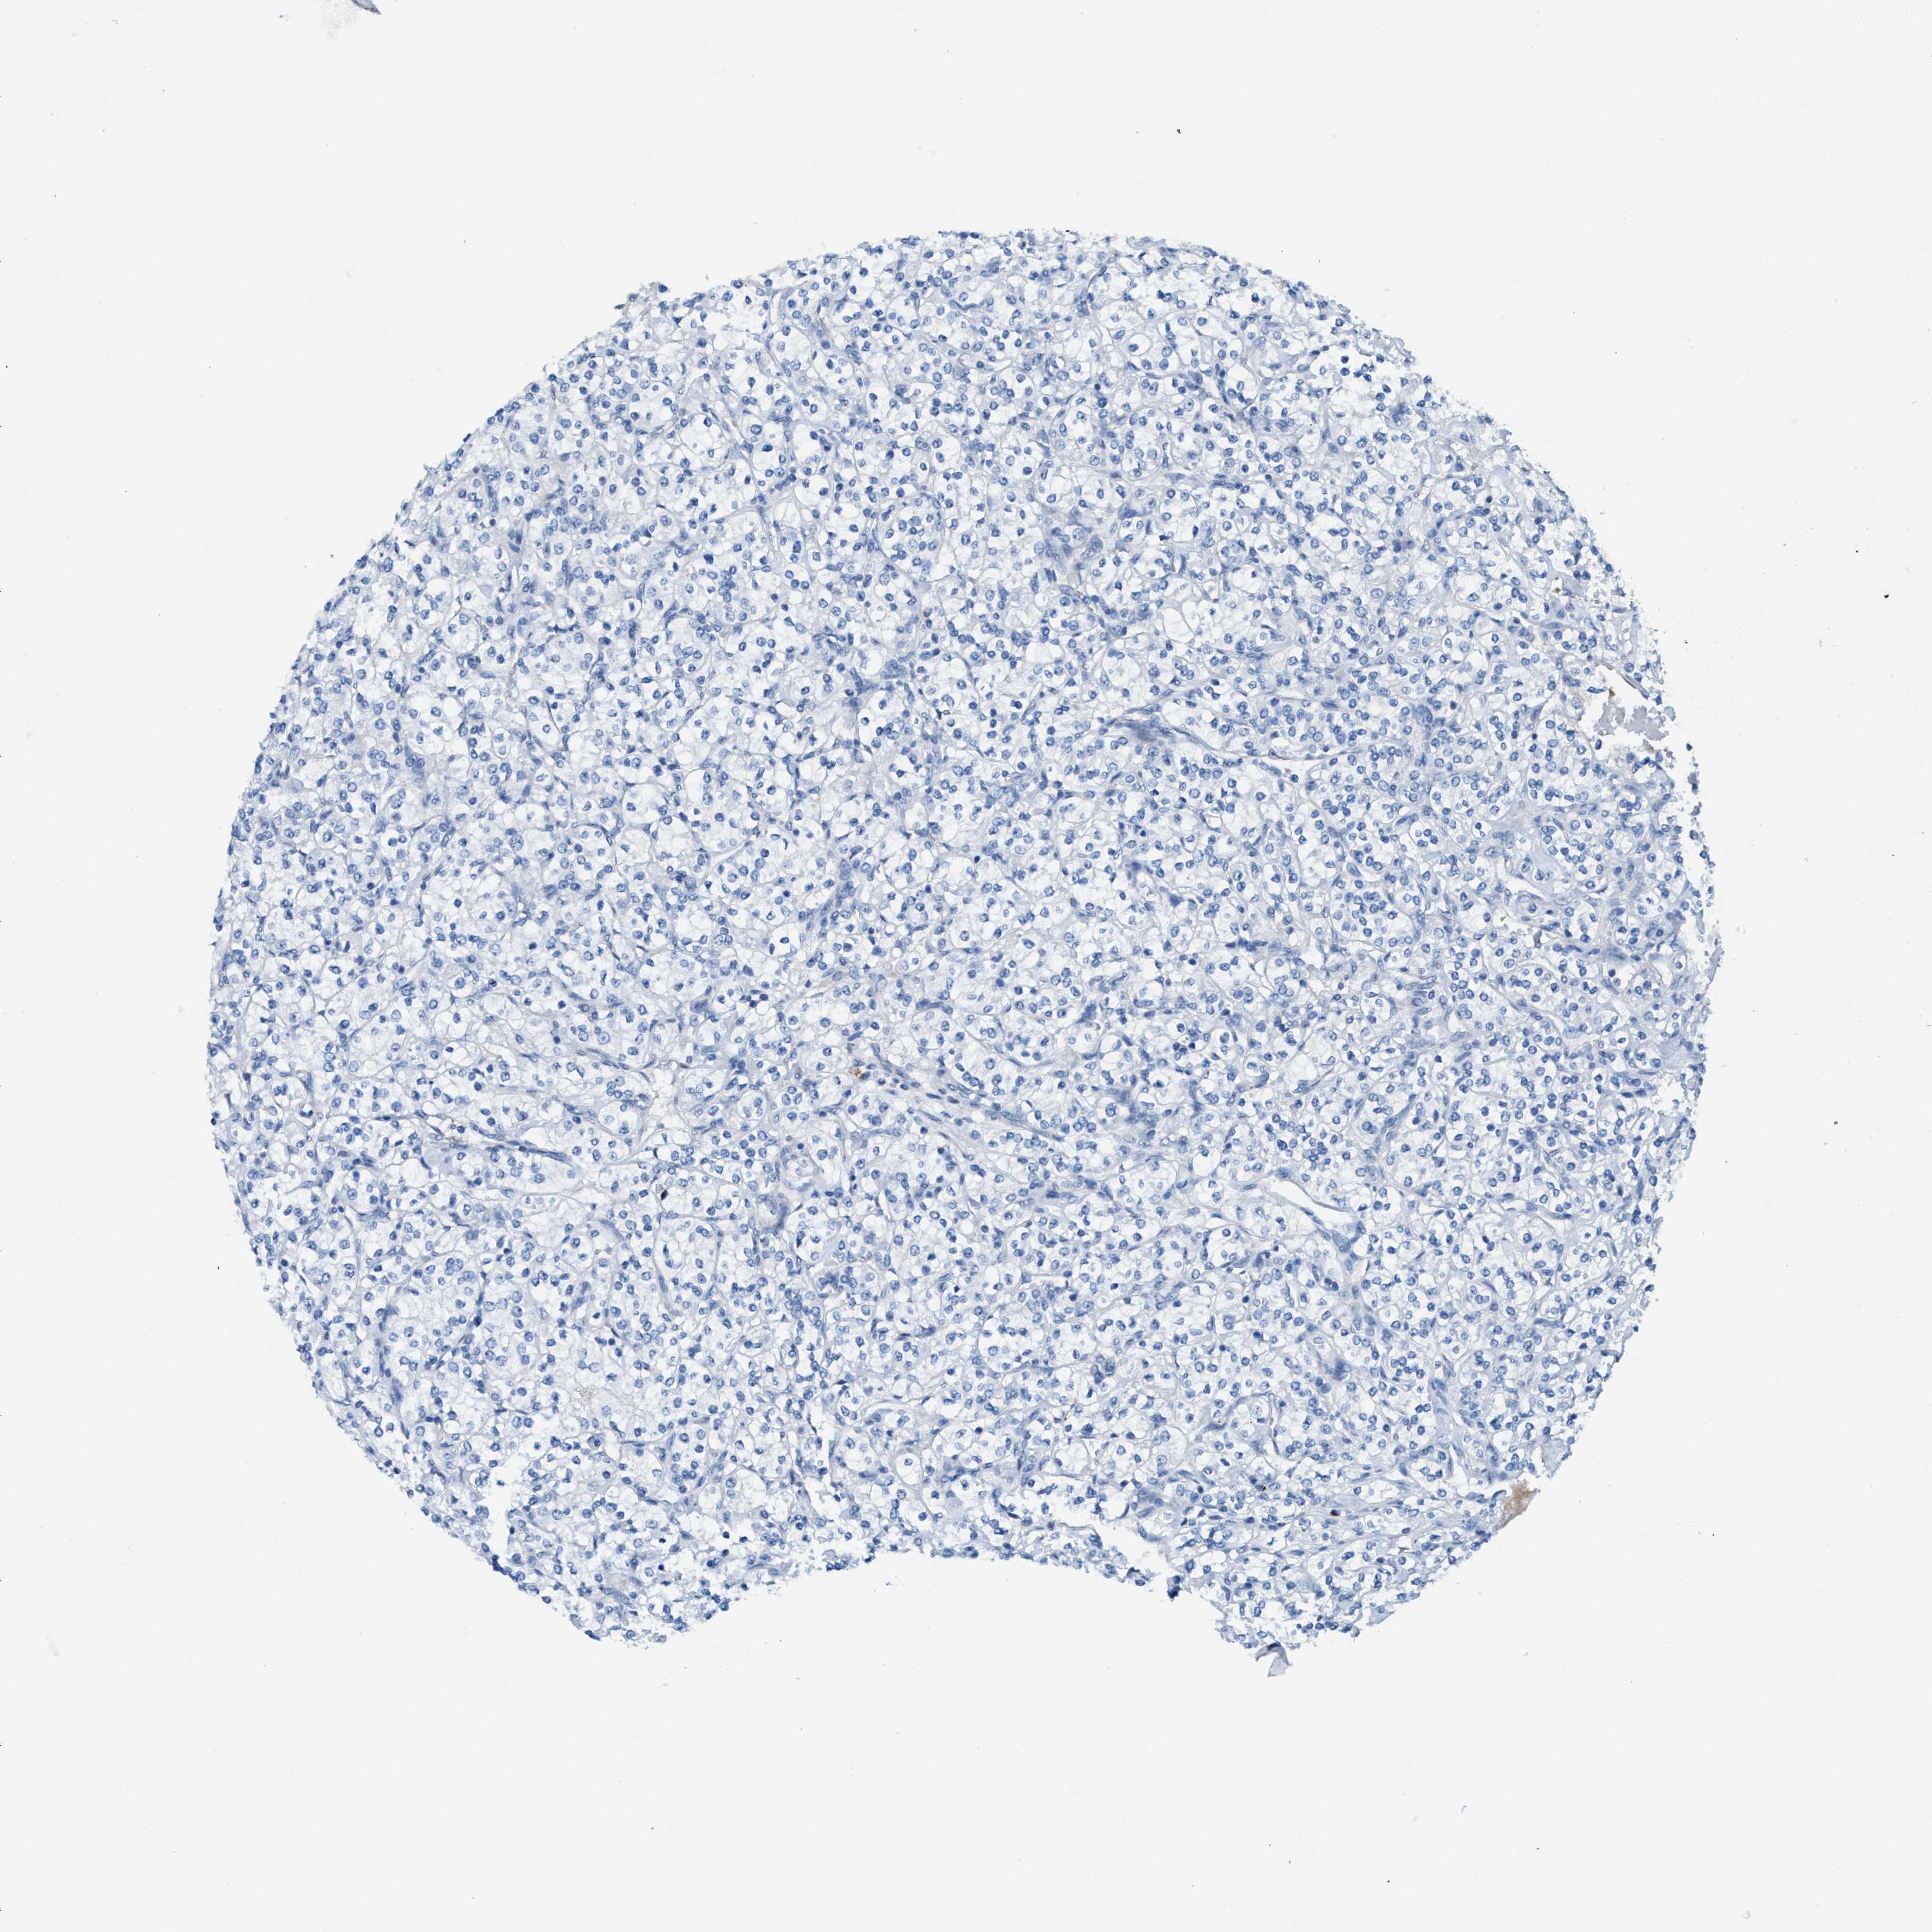

CANCER RENAL CANCER Show tissue menu

KICH TCGA KIRC TCGA KIRC VALIDATION KIRP TCGA PROTEIN RCC CPTAC PROTEIN EXPRESSION